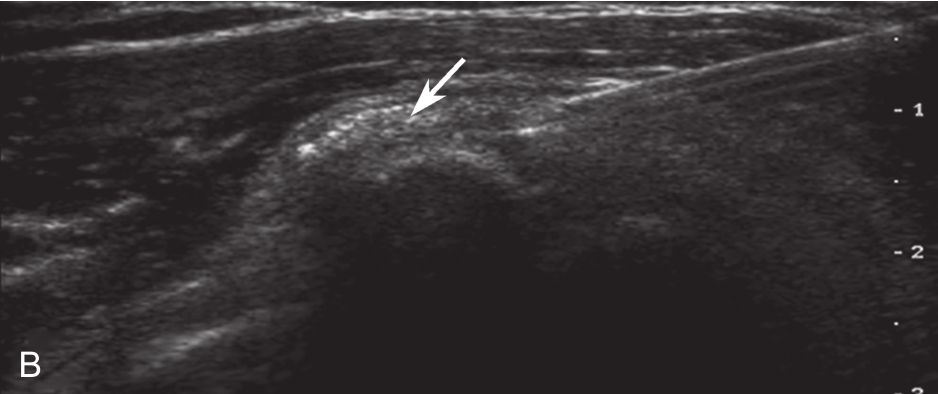

▲ 图2-2-6 超声引导下肩袖钙化性肌腱炎冲洗治疗

A.右侧冈上肌腱内钙化灶;B.超声引导下穿刺冲洗;C.注射器内为抽出的钙化灶,呈乳白色黏稠液体;D.生理盐水反复多次冲洗,可见冲洗液体逐渐变清亮;E.介入治疗前钙化灶X线片;F.治疗后钙化灶明显缩小;箭头:钙化灶